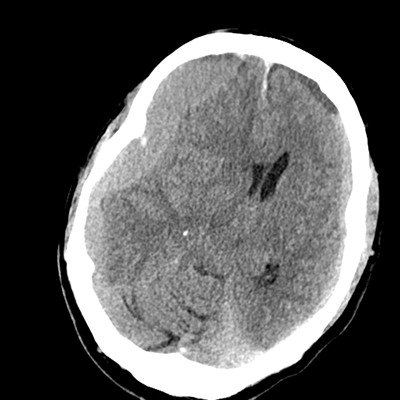

In the ED, initial vitals are notable for BP 118/68, HR 75, SpO2 97%, T37.4C. He was sent to the scanner for a pan-scan. His non-contrast head CT is shown. The ED consults you. They note that he's awake and hemiparetic. You make your way to the ED from the other side of the hospital.

NCHCT

NCHCT 1/15 1/15

NCHCT 2/15 2/15

NCHCT 3/15 3/15

NCHCT 4/15 4/15

NCHCT 5/15 5/15

NCHCT 6/15 6/15

NCHCT 7/15 7/15

NCHCT 8/15 8/15

NCHCT 9/15 9/15

NCHCT 10/15 10/15

NCHCT 11/15 11/15

NCHCT 12/15 12/15

NCHCT 13/15 13/15

NCHCT 14/15 14/15

NCHCT 15/15 15/15

What do you make of his head CT?

The most overt abnormality is the right holohemispheric extraaxial blood; it's subdural in location. The density there suggests that this is an acute finding, fitting the clinical history. There's leftward midline shift as a result, with effacement of the right lateral ventricle. The left side also has a holohemispheric SDH, though smaller in thickness. However, on this side, the SDH is layering, with more isodense blood anteriorly. This suggests that, on this left side, his SDH is acute-on-chronic.

Aside from these obvious extraaxial abnormalities, there's another subtle finding. The patient is known to have had a prior head CT when he had his initial fall a few weeks ago, with the report noting that there was diffuse cerebral volume loss. At his age, we'd expect to see more sulcation. We don't. He doesn't because these hematomas are compressive and he's developed a little cerebral edema as well.